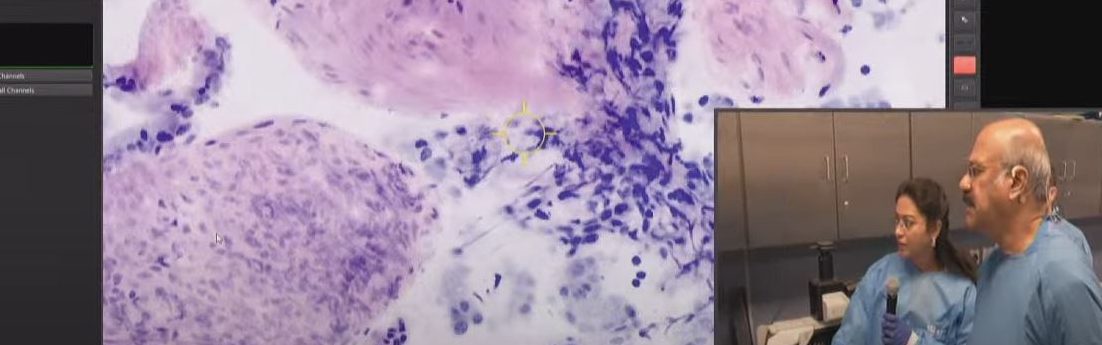

Instant Digital Pathology

Your digitalized laboratory on a cart – with VivaScope 2500. 5 minute workflow.

✔︎  Minimal Preparation

✔︎  Direct Assessment

✔︎  Tissue Integrity

✔︎  Time Savings